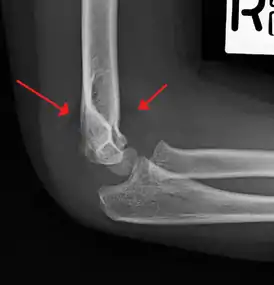

On lateral view of the elbow, there are five radiological features should be looked for: tear drop sign, anterior humeral line, coronoid line, fish-tail sign, and fat pad sign/sail sign (anterior and posterior).[3][8]

Fish-tail sign - The distal fragment is rotated away from the proximal fragment, thus the sharp ends of the proximal fragment looks like a shape of a fish-tail.[8]